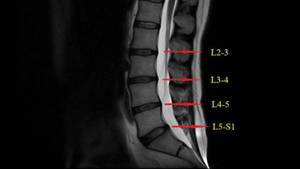

马尾综合症的机制大多数是由腰椎劳损、创伤、超负荷的腰椎牵引等因素,使突出物从后纵中突向椎管,压迫两侧的神经根和突出平面以下的马尾神经导致脑脊液循环障碍,而出现神经充血、水肿以及蛛网膜黏连,引起恶性循环,使症状更加严重。 它的神经根和放射部位的对应关系表现为:腰三神经根受压时,根性放射部位在膝部,腰四神经根受压时,根性放射部位在小腿以下,腰五神经根受压时,根性放射部位在足背和踝,骶一神经根受压时根性放射部位在足跟和足底,骶二神经根受压时根性放射部位在下肢后侧和大腿内侧方,骶三神经根受压时根性放射部位在外生殖器和肛门周围。常见的马尾综合征病因有哪些?